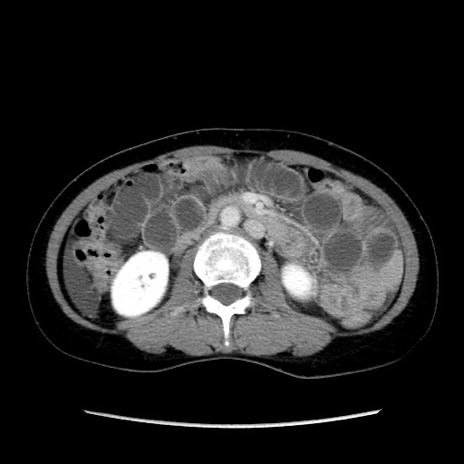

症例32(横断像)

【症例】40歳代 女性

【主訴】上腹部痛、嘔気・嘔吐

【現病歴】約9時間前頃から急に上腹部痛、嘔気、嘔吐が出現。改善しないため救急要請。

【既往歴】子宮頚癌(広汎子宮全摘術、放射線療法)、腸閉塞

【身体所見】腹部:平坦、軟、腸雑音亢進、上腹部を中心に腹部全体に圧痛あり。

【データ】WBC 8400、CRP 0.03